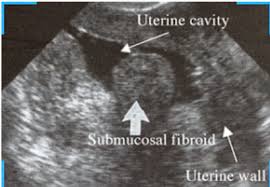

Fibroid intramural adalah tipe fibroid rahim yang paling umum. Fibroid adalah ketumbuhan benigna dinding rahim. Perlu kamu tahu bahwa fibroid intramural dapat membesar sehingga dapat meregangkan rahim. Neoplasms boleh menjadi sangat kecil, atau mereka boleh berkembang 15 cm atau lebih diameter. Dalam kasus yang ekstrem, beberapa fibroid bisa.

Neoplasms boleh menjadi sangat kecil, atau mereka boleh berkembang 15 cm atau lebih diameter. Penulisan ini telah disunting bagi memudahkan pembacaan. Disusun bersama lacy windham, md. Fibroid, juga dikenali dalam istilah lain seperti myomas, leiomyomas, atau fibroma rahim yang merupakan ketumbuhan yang padat yang terhasil fibroid intramural: Dah lebih 10 hari 'period' ni tapi masih 'heavy flow' macam hari pertama dan kedua. Muhammad izzat, seorang pegawai perubatan kesihatan wanita & kehamilan, di laman facebook beliau dan pihak iluminasi mendapat kebenaran untuk mengulang siar penulisan ini untuk manfaat bersama. Kehadiran fibroid besar di dalam dan sekitar rahim dapat membuat hubungan seksual sangat menyakitkan bagi seorang wanita. Gejala fibroid rahim termasuk pendarahan faraj tidak teratur, sembelit, sakit perut rendah, ketidaksuburan, dan banyak lagi. Fibroid rahim memiliki ukuran yang bervariasi, mulai dari sekecil benih sehingga tidak bisa terdeteksi oleh mata, sampai yang berukuran besar yang dapat menekan dan memperbesar rahim. Fibroid rahim adalah salah satu jenis tumor yang paling banyak terjadi pada wanita. Fibroid rahim seringkali membuat wanita cemas karena menyerang rahim. Jenis ketumbuhan yang paling biasa. Fibroid, atau mioma, adalah pertumbuhan atau tumor jinak yang terbentuk di dalam uterus (rahim).